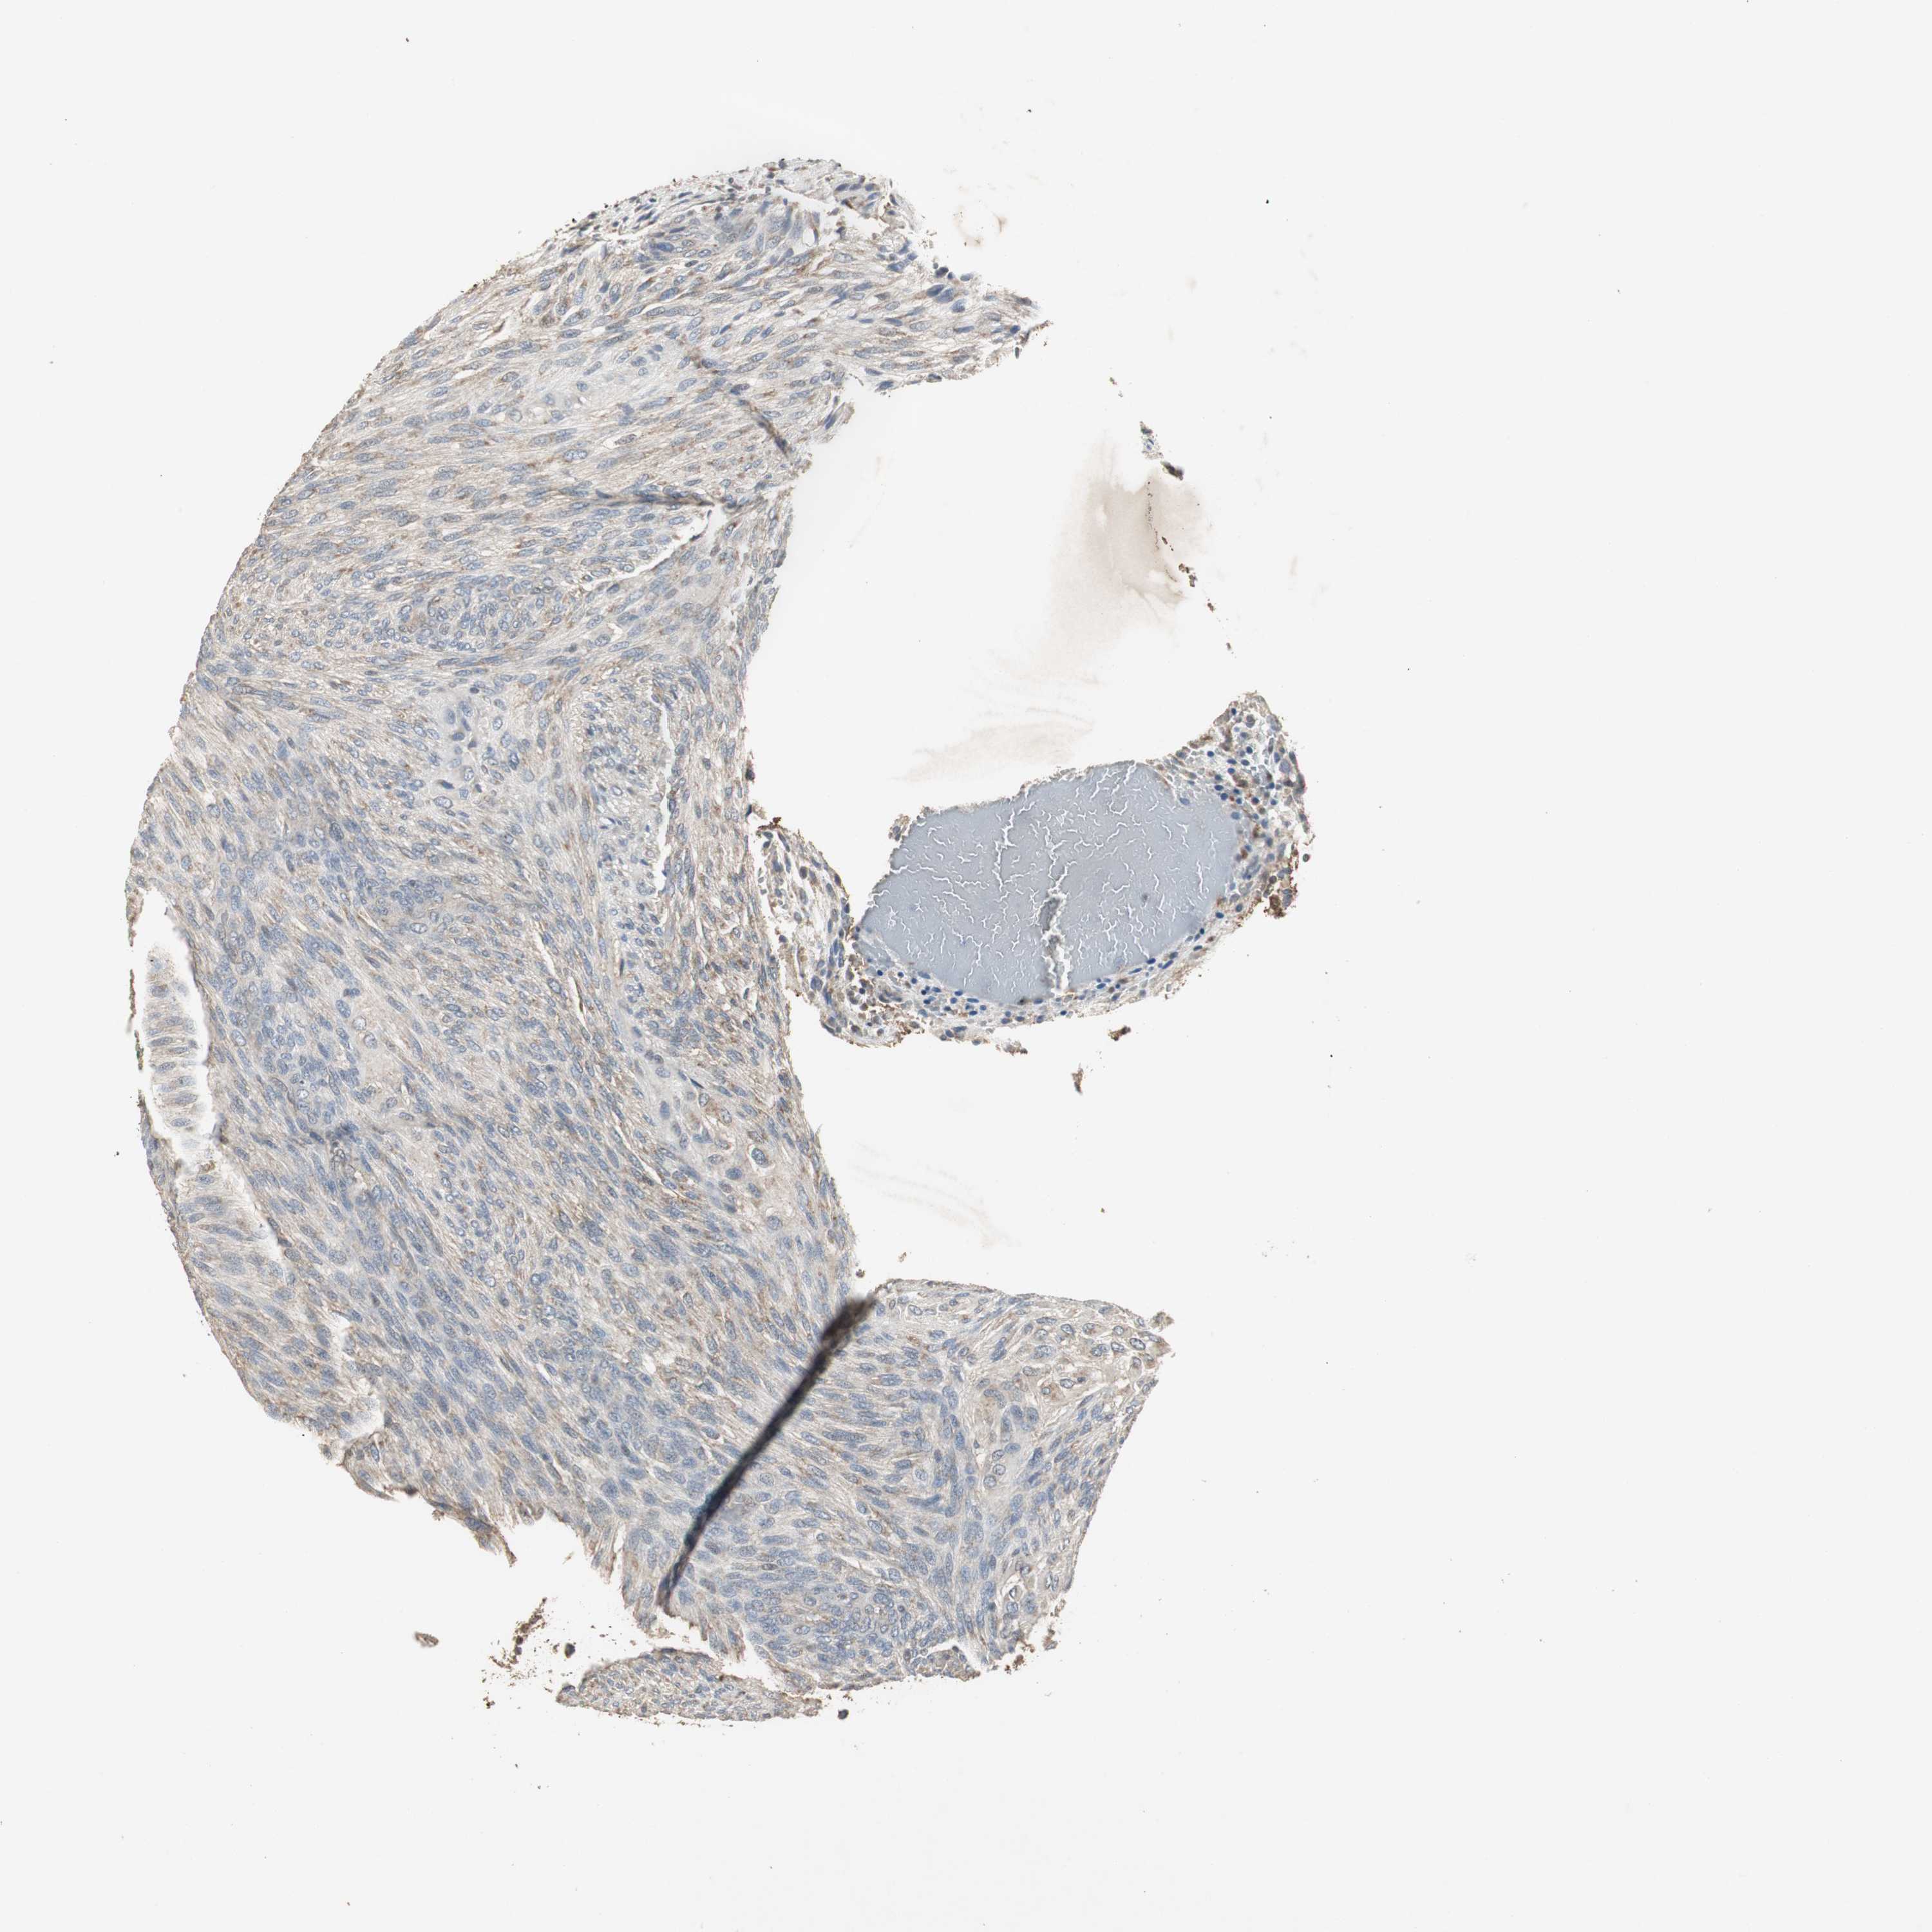

GLIOMA - Protein expressioni

A mouse-over function shows sample information and annotation data. Click on an image to view it in a full screen mode. Samples can be filtered based on level of antibody staining by selecting one or several of the following categories: high, medium, low and not detected. The assay and annotation is described here.

Note that samples used for immunohistochemistry by the Human Protein Atlas do not correspond to samples in the TCGA dataset.

Antibody stainingi

Antibody staining in the annotated cell types in the current human tissue is reported as not detected, low, medium, or high, based on conventional immunohistochemistry profiling in selected tissues. This score is based on the combination of the staining intensity and fraction of stained cells.

Each image is clickable and will lead to virtual microscopy that enables deeper exploration of all samples and also displays staining intensity scores, fraction scores and subcellular localization as well as patient and tissue information for each sample.

Antibody HPA006514

Staining

High

Medium

Low

Not detected

Intensity

Strong

Moderate

Weak

Negative

Quantity

>75%

75%-25%

<25%

None

Location

Nuclear

Cytoplasmic/membranous

Cytoplasmic/membranous,nuclear

Glioma, malignant, High grade

Glioma, malignant, NOS